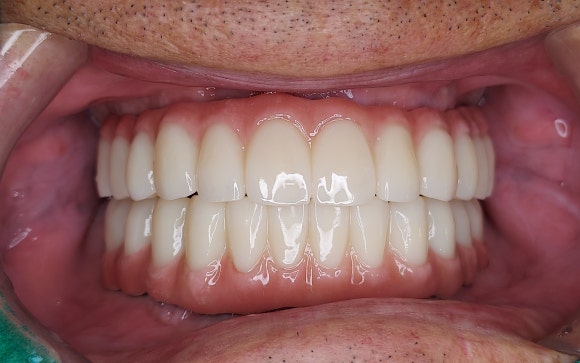

어금니 상실은 저작 기능 저하로 이어져

소화 불량 및 영양 불균형을 초래할 수 있습니다.

잇몸 뼈가 부족하여 임플란트가 어렵다는

진단을 받으셨더라도 뼈이식을 통해

충분히 기능을 회복할 수 있습니다.